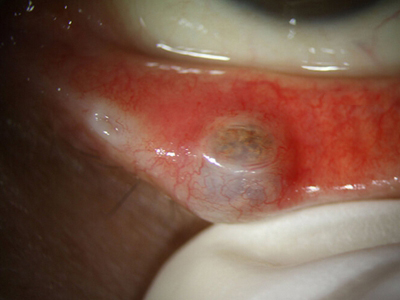

眼睑皮脂腺癌是起源于睑板腺和皮脂腺的一种眼睑腺癌。本病多见于中老年女性,好发于上睑,通常表现为结节,逐渐可变为黄色隆起,会出现溃疡或菜花状,一旦确诊,多需手术治疗。

眼睑皮脂腺癌是我国常见的眼睑恶性肿瘤之一,常起源于睑板腺和睫毛皮脂腺。如起自睑板腺,初起时为眼睑皮下小结节,与睑板腺囊肿相似,以后逐渐增大,睑板弥漫性斑块状增厚,睑结膜呈黄色隆起。如起自皮脂腺,则在睑缘呈黄色小结节,表面皮肤正常。部分患者的肿瘤呈派杰样浸润生长,易误诊为结膜炎。当肿块逐渐增大后可形成溃疡或呈菜花状。